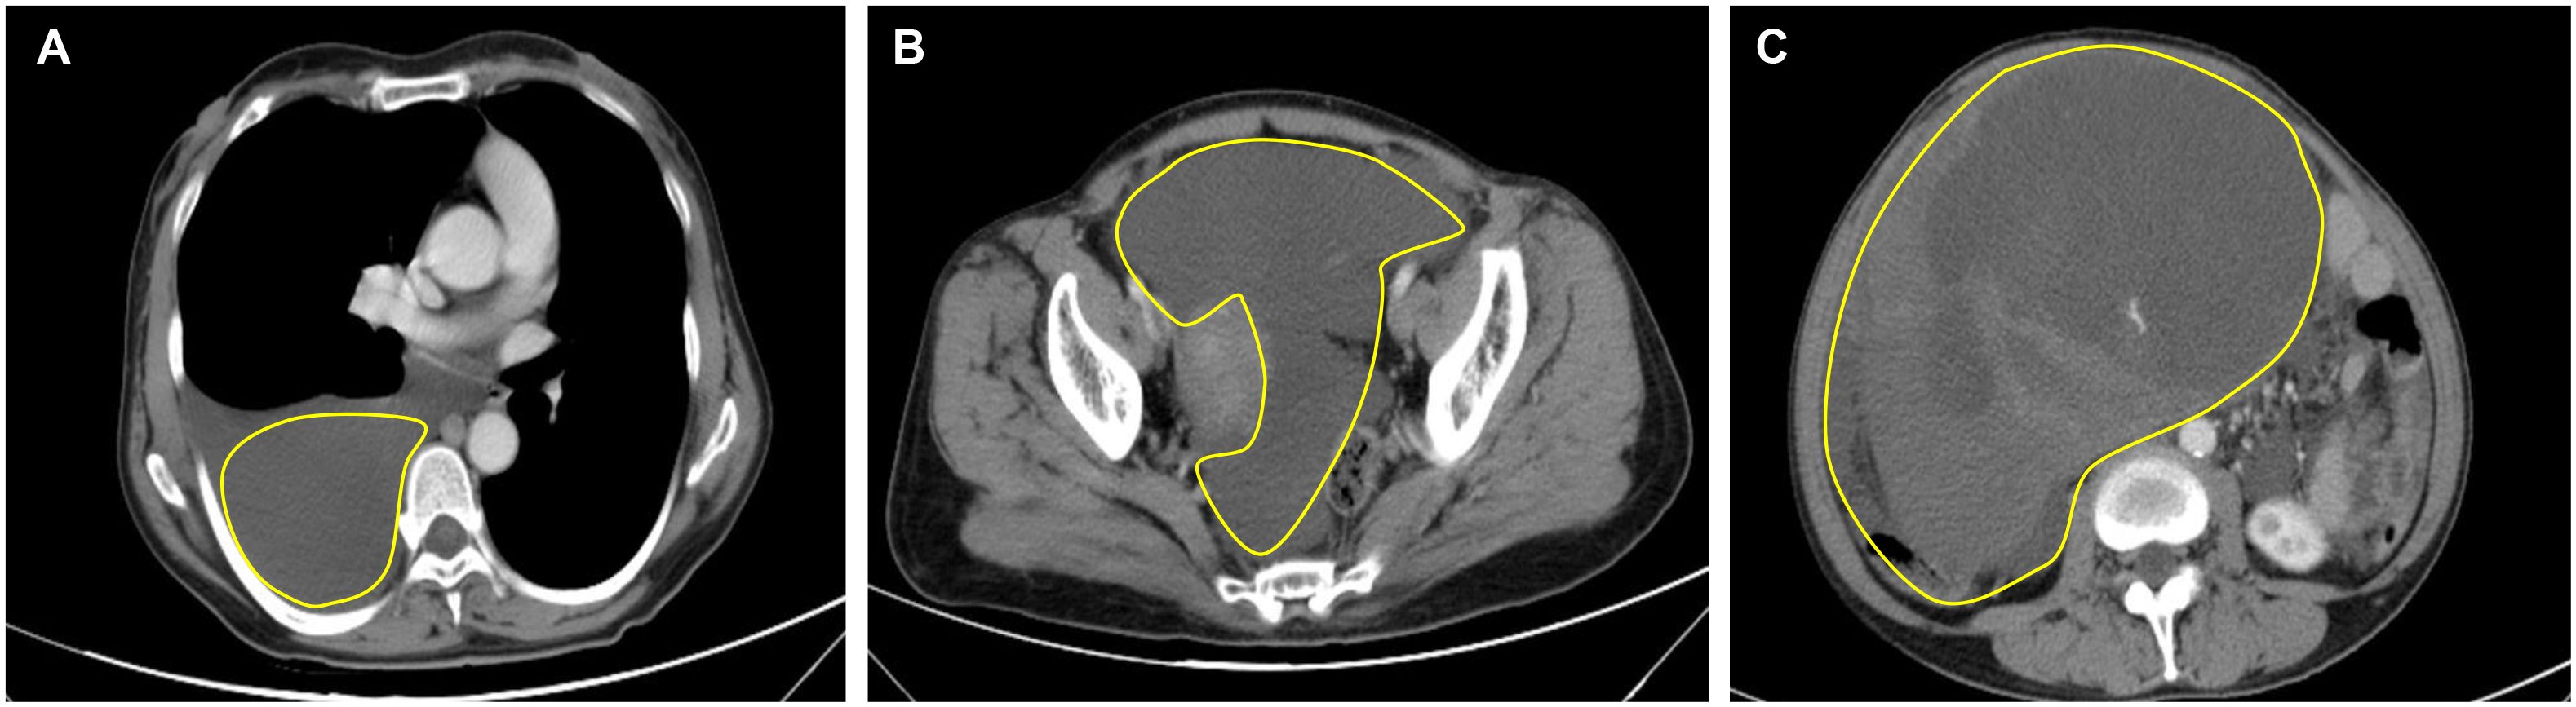

Computed tomography (CT) of the chest showed significant pleural effusion and ascites, (Figures 1A, B). Transverse view of the abdomen showed a large solid mass measuring 21.5 × 14.6 cm (Figure 1C).

Figure 1. Preoperative CT of the thorax and abdomen. (A) CT thorax showed right-sided pleural effusion; (B) Abdomen CT showed ascites; (C) Transverse view of the abdomen shows a large solid tumor measuring 21.5 × 14.6 cm.